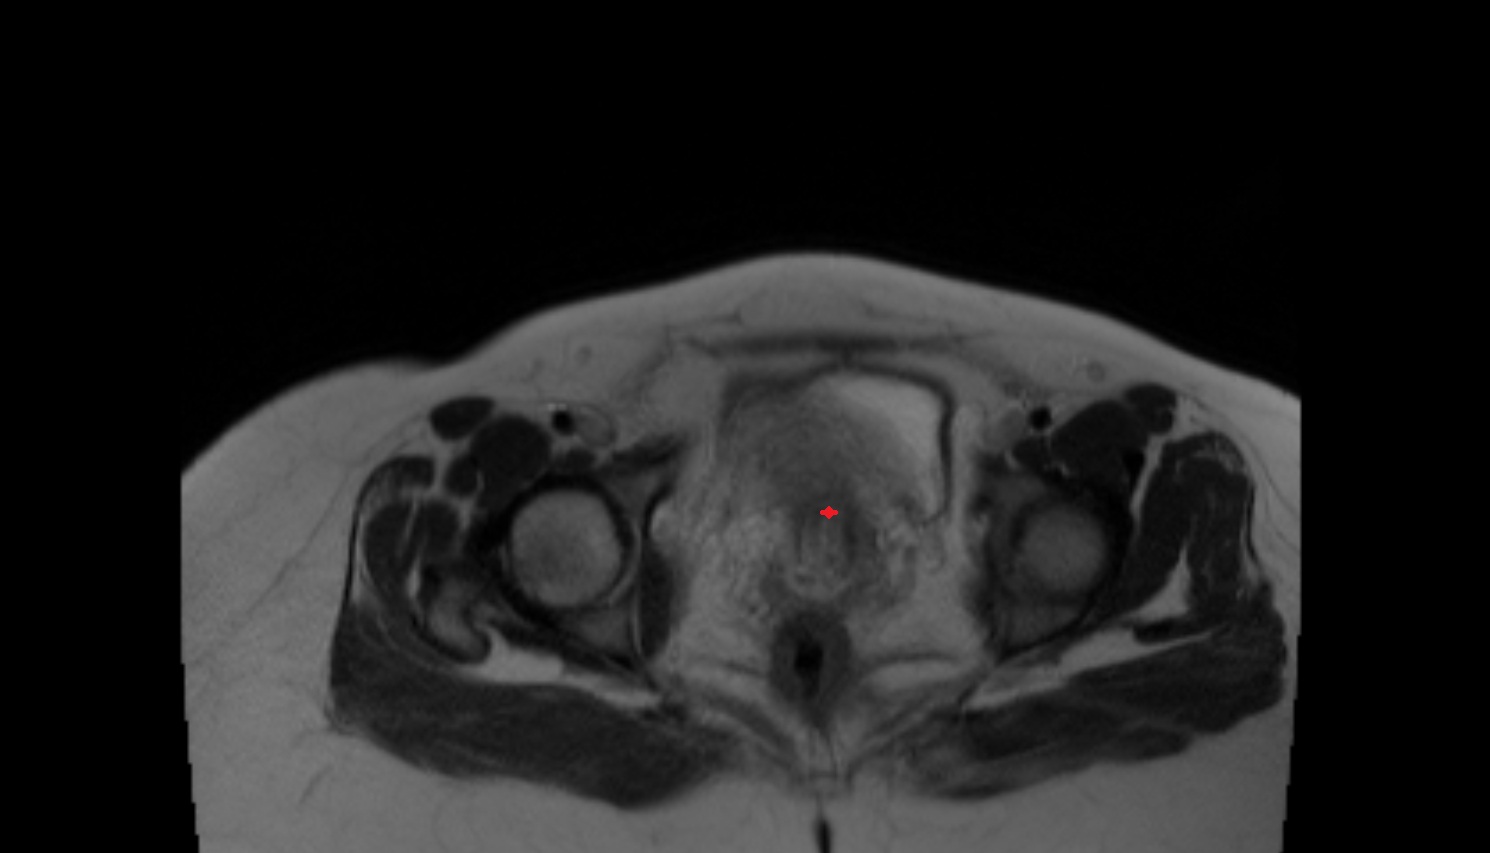

- Mons pubis

- Labia majora

- Labia minora

- Clitoris